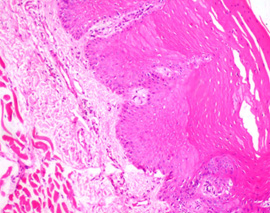

Fixation of tissues in 10% formalin solution gave the ideal results [Table/Fig-2] which acted as the positive control for the study. All the transit fixatives were able to preserve the tissue over a period of 8 h. Tissue fixed with L.A. [Table/Fig-3] and H2O2 [Table/Fig-4] showed good cytoplasmic and nuclear details. Similarly, in honey [Table/Fig-5] fixed tissue sections, the cytoplasmic and nuclear details were satisfactory. Difficulty was encountered while sectioning the Betadine fixed tissues which resulted in folded artifacts. On the other hand, tissue in saline showed significant cellular swelling & poor staining with H & E, which indicates tissue autolysis. Other tissue sections had good overall morphology and also good nuclear, cytoplasmic details and staining quality except saline and spirit. To sum up the overall results, the tissue fixation ability was in the following order: Formalin > L.A > H2O2> Honey> Coconut oil [Table/Fig-6] > Rose water> Coconut water > Milk> Betadine> Ice cold water> Saline> Spirit.

Hematoxylin & Eosin section of tissue fixed in COCONUT OIL prior to formalin